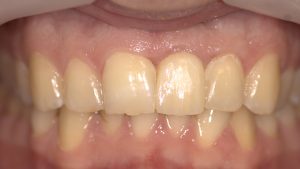

Level 1 Case: Socket shield technique

initial state Surgical stage after initial healing Final Restoration The future of the aesthetic zone…